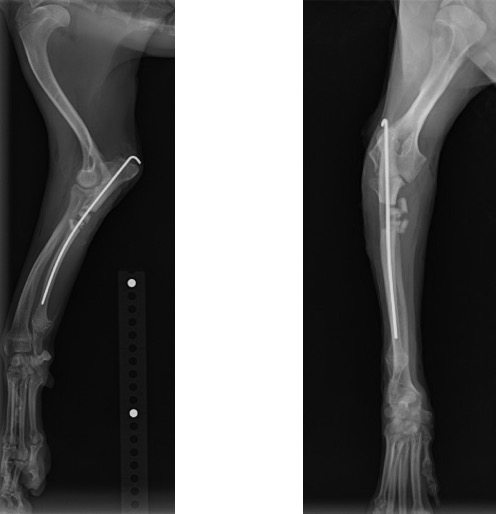

単純X線画像検査において、右側の尺骨遠位成長板領域の不透過性亢進、橈骨の頭側湾曲、鈎状突起と上腕骨顆の間隙が広がっている所見が認められたため、尺骨遠位成長板早期閉鎖が疑われました。

術前計画としてCT検査を実施し、肘関節の整合性を確認した後に、橈骨の湾曲防止と肘関節の不整合を矯正するために尺骨の骨切術を実施しました。

術後のLateral像とAP像 (骨切り後に尺骨のアラインメントを合わせるために髄内ピンとして1.2mm K-wireを刺入しました)